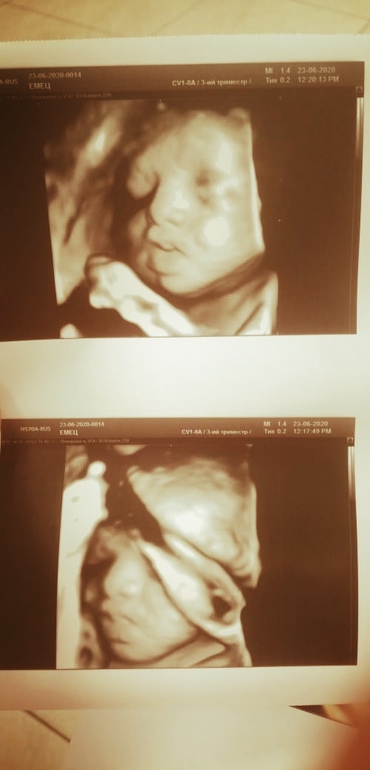

УЗИ 35+0 недель❤️❤️❤️

Мы растём !)) 12 недель 2 дня, 1 скриннинг